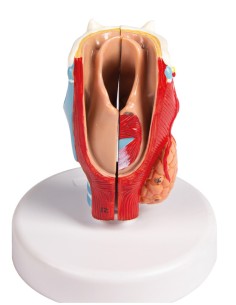

3B Scientifique, modèle anatomique du larynx, deux fois agrandi, en 7 parties G21

3B Modèle anatomique scientifique et fonctionnel du larynx : W42503